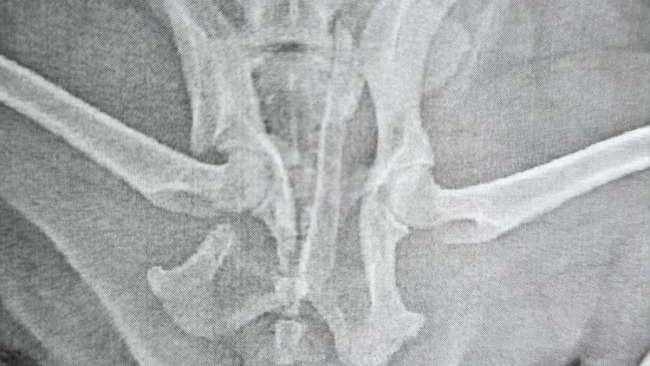

Tango (imię schroniskowe) przyjechał do nas z innej lecznicy do której trafił po wypadku. Odpowiednio zaopatrzony i zaopiekowany przyjechał z paskudną diagnozą - złamanie kości miednicy. Szybka burza mózgów, kontakt z lecznicami, kontakt z rehabilitantami i udało się znaleźć odpowiednie miejsca dzięki którym psiak w przyszłości będzie mógł wrócić do pełnej sprawności.

Tango wie, że nie zostawimy go bez pomocy, ale niestety ta pomoc jest kosztowna. Koszty samego zabiegu opiewają na blisko 2000 złotych. Do tego dochodzą jeszcze koszty opieki medycznej oraz rehabilitacji. Część z tych środków jesteśmy w stanie pokryć. Jednak nie wszystko. Dlatego zwracamy się do Was - zwierzolubów, ludzi, których los zwierząt nie jest obojętny. Organizujemy zbiórkę na operację Tango i wierzymy, że pieniądze nie staną na przeszkodzie pełnego powrotu do zdrowia tego urwisa. Ten młody psiaczek jeszcze niewiele w życiu widział a już musiał tyle wycierpieć Wspólnymi siłami możemy dać mu jeszcze wiele lat szczęścia Możemy na Was liczyć? Zamieszczamy zdjęcia Tango wraz ze zdjęciami RTG jako (jak to mawiają w policji) dowód w sprawie